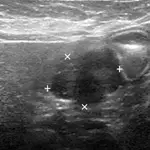

Figure 2: Ultrasound image of the pancreatic mass; the pancreatic mass is a hypoechoic irregular nodule outlined by the + and x markers

Thoracic radiographs showed no abnormalities. Abdominal ultrasound revealed a hyperechoic nodule in the liver, and the liver had rounded margins (image not shown). The pancreas had enlarged irregular borders with mixed echotexture and a mass in the right lobe (Figure 2).